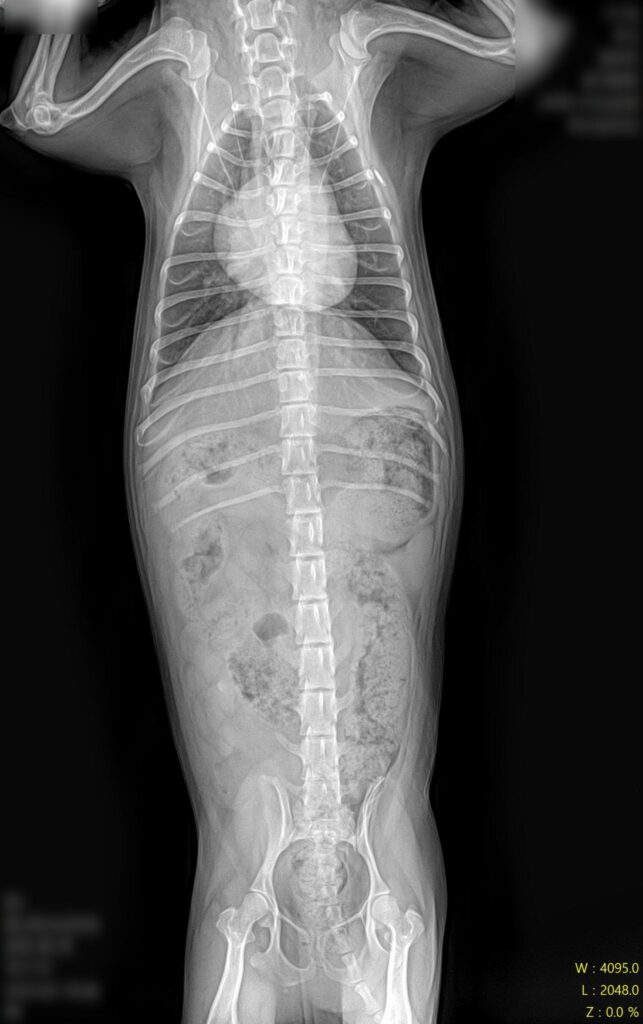

마취 전 방사선 검사 / 출처: 라온동물메디컬센터

정형학적 검사와 방사선 영상 검사를 진행한 결과, 슬개골탈구 4기(말기, terminal) 소견이 확인되었습니다. 슬개골이 완전히 고정 탈구된 상태였고, 활차구의 심각한 평탄화와 경골 조면의 내측 편위, 다리뼈의 비틀림이 동반되어 있었습니다.

2년 전 3기 진단 당시와 비교하면 그 사이 조용히, 그러나 빠르게 진행된 것이었어요. 보행이 크게 불편해 보이지 않았던 이유는 강아지가 변형된 뼈 구조에 스스로 적응하며 걷고 있었기 때문입니다.